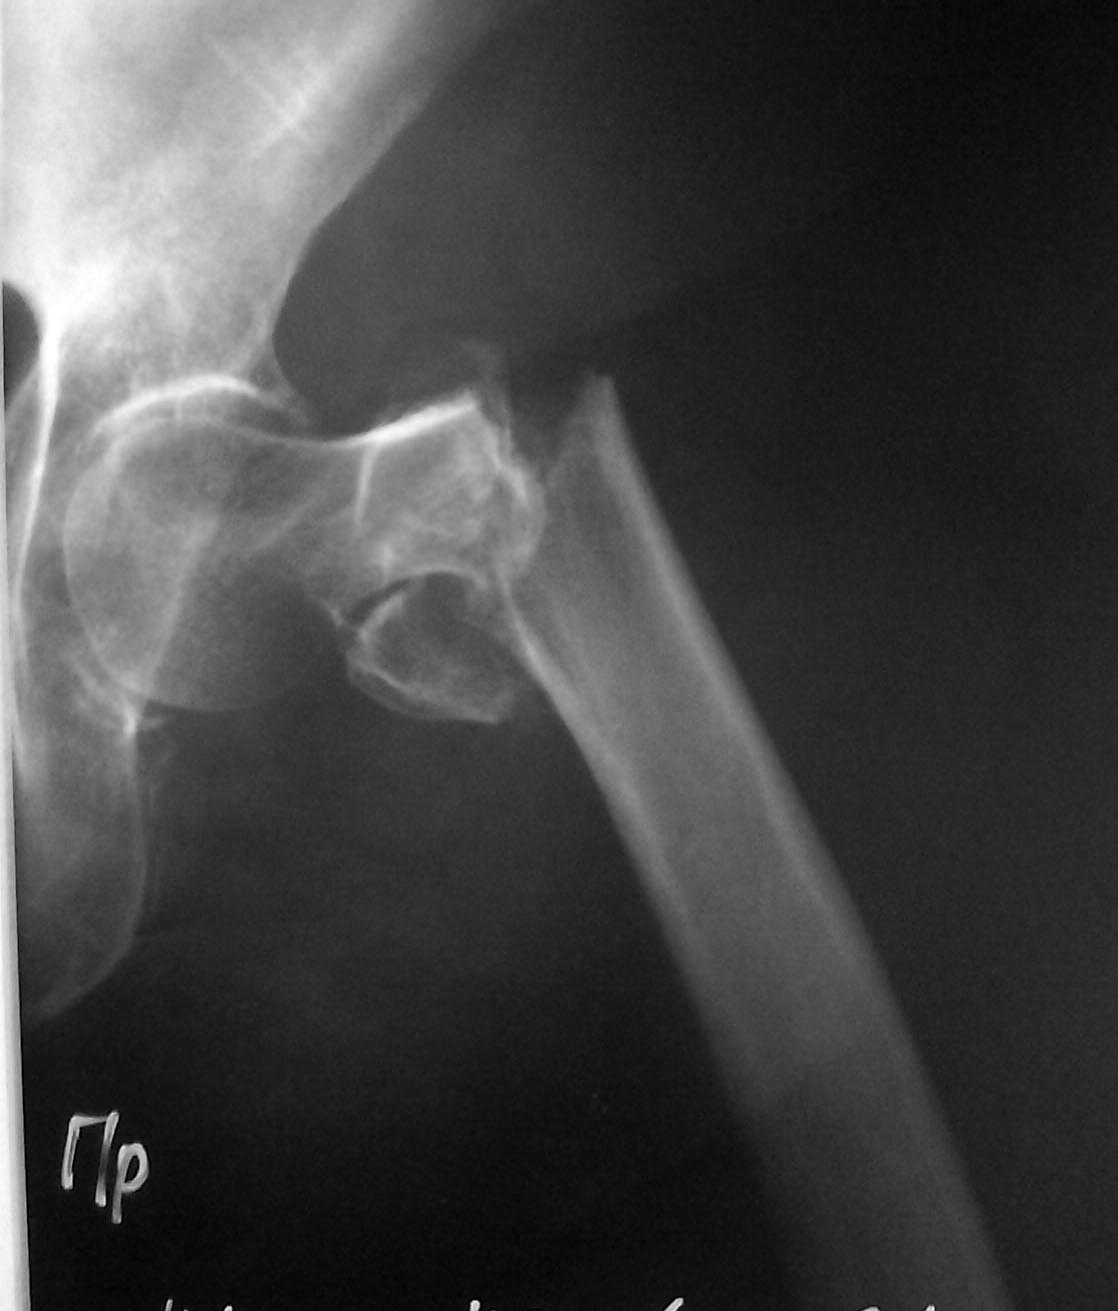

[Ortho] Чрезвертельный перелом

Больная 77 лет чрезаертельный перелом, коллегам просьба помочь в выборе

метода лечения